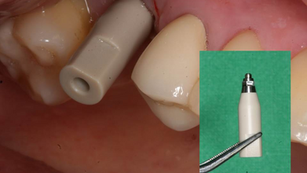

Intraoral Scanning System using a Scanbody

Situation Implant placement on the missing area #16 was planned. Pre-operative Radiograph Panoramic radiograph was taken after an implant...

Dr. YoungKu Heo

Dec 28, 20151 min read